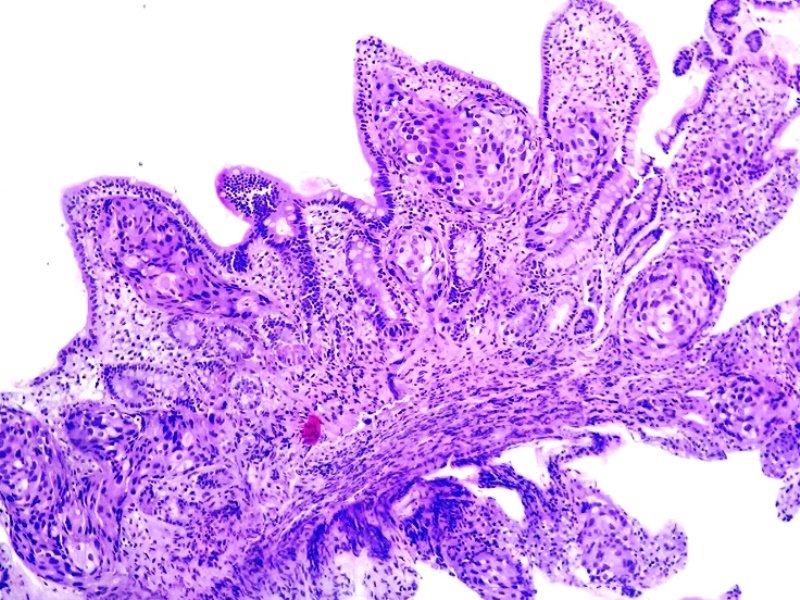

Anapat@Anapat_Lab·

Vejiga. Carcinoma papilar urotelial invasor.